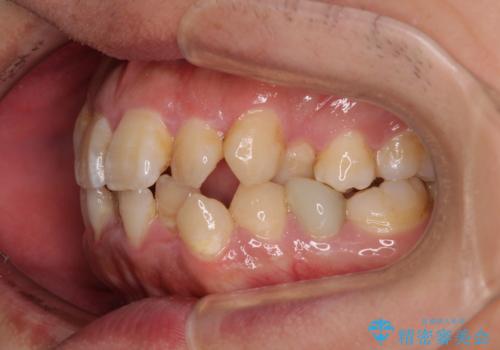

- 「歯並び全体のデコボコをきれいに整えたい」とのご希望で、20代男性の患者様が来院されました。

特に前歯部の叢生(歯の重なり)が強く、見た目だけでなく歯磨きのしにくさも気にされていました。

診査の結果、上下前歯に強い叢生が認められ、歯をきれいに並べるためのスペースが明らかに不足していました。

無理に歯を並べると、前歯が前方に突出するため、抜歯によるスペース確保が必要と判断しました。